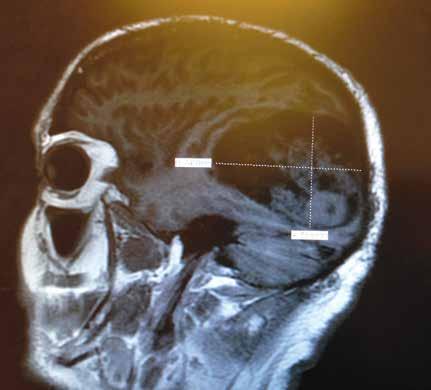

Gaye Stephenson O’Callahan (June 6, 1947 – May 28, 2024) passed away on the evening of May 28th after a two year fight with brain cancer.

Gaye was born in Los Angeles, California, the first child of Willam Hughes Stephenson and Phyllis Vera Gay Stephenson. The family, now 4 children, moved to Santa Barbara when Gaye was seven. She attended Hope School, La Colina Jr. High and San Marcos High School where she had many fond memories, being involved in many activities while there.

After attending San Marcos High School, she went to Stephen’s College in Missouri for one year, then returned to Santa Barbara to earn her BA in anthropology at Santa Barbara City College and UCSB. She was a flight attendant for Hughes Air West for several years, based in Phoenix, where she met and married her husband, Jerry. They had two boys, Kevin (Napa) and Shawn (Superior, CO) living in several locations – Tempe, Glendale, CA and Spokane. They divorced and Gaye returned to Santa Barbara to raise the boys. She worked almost 30 years as a loan processor with Paragon Mortgage. And to the delight of her high school classmates, she helped organize the database of information on the where abouts of them as well as helped organize the reunions. While she loved to play bridge – participating in 3 bridge groups – as well

as doing jigsaw puzzles, reading and traveling, her greatest source of pleasure was the natural world around her. Her love of nature began in her youth when her family would take week long hikes in Yosemite during the summers. She more recently completed this loop hike with Kevin.

With our hearts saddened, she leaves behind two sons, Kevin (Gina) and Shawn, and 3 grandchildren (Bailey, Kiera and Eva) as well as her 3 siblings Andy (Cindy), Lynne (Bob) and Jim (Cathy). In lieu of flowers, please consider donating in Gaye’s memory to the Santa Barbara Botanic Gardens. A memorial service will be held at a later time. For more information feel free to reach out to the family.